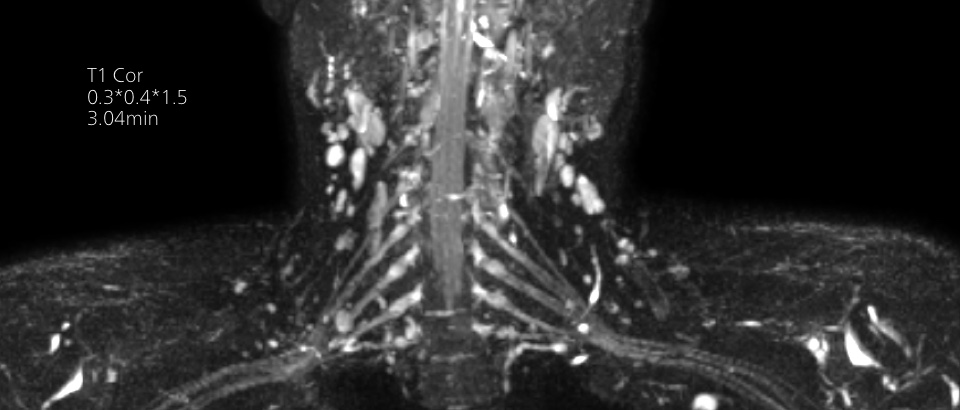

Turn images into answers – 50% faster

Put time on your side with Compressed SENSE to reduce scan time up to 50%2 with virtually equal image quality. Create exceptional MR images with 60% higher resolution for confident diagnosis.

Quality images for quality diagnoses

Our lightest Breeze coils bring extraordinary versatility to imaging challenging anatomies and the smallest joints. A large 55cm field-of-view and premium SNR add to the exceptional image quality.